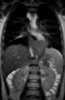

Esophageal leiomyomatosis

A leiomyoma, also known as fibroids, is a benign smooth muscle tumor that very rarely becomes cancer (0.1%). They can occur in any organ, but the most common forms occur in the uterus, small bowel, and the esophagus. [Source: Wikipedia ]